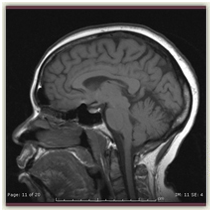

MRI= Exquisite Anatomic Detail

is a safe, painless, and potentially one of the most accurate, non-invasive procedures available to obtain images of the body. In many cases, a high quality MRI reveals exquisite anatomic detail and eliminates the need for additional diagnostic procedures.

In MRI, a magnet is used in conjunction with radio waves and a sophisticated computer system to generate accurate images of the body without using any radiation. MRI is frequently used to study muscles, joints, the brain and spine, the abdomen, pelvis, chest and blood vessels.

Imaging of the Head and Spine. MRI for neurological/brain imaging and spine studies provides outstanding image quality for diagnosis. The MRI software offers many mode and viewing options including the ability to reconstruct and rotate images to show soft tissue of the brain. MRA studies offer enhanced images of vascular structures.